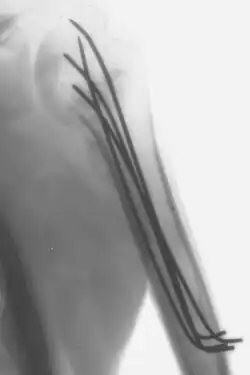

Kirschner wires or K-wires or pins are sterilized, sharpened, smooth stainless steel pins. Introduced in 1909 by Martin Kirschner, the wires are now widely used in orthopedics and other types of medical and veterinary surgery. They come in different sizes and are used to hold bone fragments together (pin fixation) or to provide an anchor for skeletal traction. The pins are often driven into the bone through the skin (percutaneous pin fixation) using a power or hand drill. They also form part of the Ilizarov apparatus.

- They can be used for definitive fixation if the fracture fragments are small (e.g. wrist fractures and hand injuries). In some settings they can be used for intramedullary fixation of bones such as the ulna.